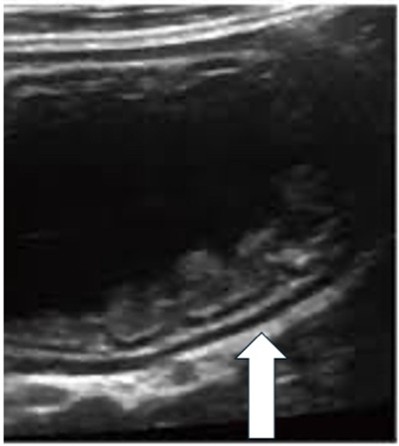

![]() |

Arrow indicates PVG identified as echogenic bubbles in the liver |